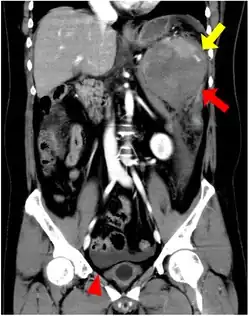

| CT scan of an accessory spleen (circular object in center of image) between the spleen and left kidney. | |

An accessory spleen is a small nodule of splenic tissue found apart from the main body of the spleen. Accessory spleens are found in approximately 10 percent of the population[1] and are typically around 1 centimeter in diameter. They may resemble a lymph node or a small spleen. They form either by the result of developmental anomalies or trauma.[2] They are medically significant in that they may result in interpretation errors in diagnostic imaging[2] or continued symptoms after therapeutic splenectomy.[1] Polysplenia is the presence of multiple accessory spleens rather than one normal spleen.

If splenectomy is performed for conditions in which blood cells are sequestered in the spleen, failure to remove accessory spleens may result in the failure of the condition to resolve.[1] During medical imaging, accessory spleens may be confused for enlarged lymph nodes or neoplastic growth in the tail of the pancreas,[5] gastrointestinal tract, adrenal glands or gonads.[2]